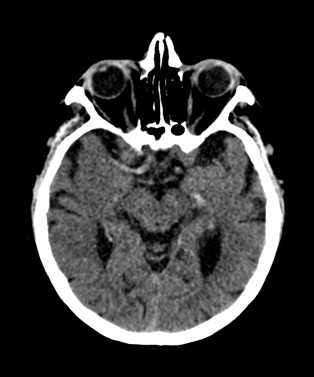

In acute phase (12-24 hours after the occlusion of the middle cerebral artery) on CT hypodense basal ganglia, the loss of cortical white-grey matter differentiation and sulcal effacement are the characteristic imaging findings.

On MRI, diffusion restriction causes hyperintense signal on T2W images. The leptomeningeal border of the infract zone will show contrast enhancement.

After 1-3 days the “mass-effect” of the infarct increases. It is more apparent in case of large territorial infarcts, the sulcal effacement completes, the loss of cortical white matter and grey matter differentiation is more pronounced (especially in the white matter) due to the increased hypodensity. Hemorrhagic transformation in the grey matter (cortex, basal ganglia) can also occur at this stage. It is worth to note, that for hemorrhagic transformation one should not always blame thrombolytic therapy; it rather occurs spontaneously in a great majority of the cases.

After 4-7 days the edema and the “mass-effect” persist, there is a marked hypodensity and even contrast enhanced CT can detect enhancement at the leptomeningeal border of the infarct zone.

Within 1-8 weeks contrast enhancement and mass-effect still persist. Later a slow regression in the mass-effect can be noted. In children (transient) calcification can also occur.

In the chronic phase of the infarct (months to years) the hypodensity of the lesion (CT) reaches the level of the cerebrospinal fluid. There is no more contrast enhancement, the lesion is well differentiated and it degenerates into a cyst secondary to encephalomalacia. The brain parenchyma experiences a volume decrease due to the degeneration (sometimes calcifications can occur at the marginal border of the infarct).